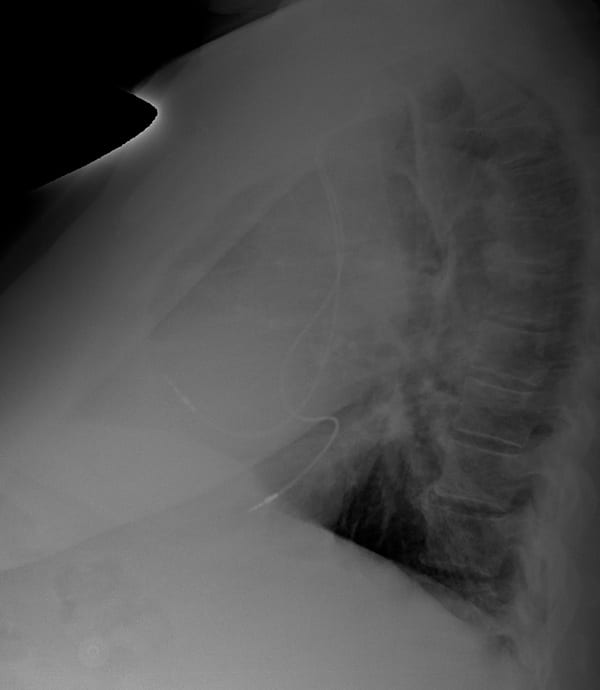

…so how about a lateral CXR?

For many of us the role of the lateral CXR is to localise or investigated pulmonary pathology, and we don’t always look at the cardiac silhouette. In this case an understanding of the lateral cardiac silhouette is essential to confirm our ECG suspected diagnosis.

Looking at this lateral CXR we can see one pacemaker lead sits anteriorly, and the other is sitting posteriorly, this is NOT normal.

On a lateral CXR the right ventricle sits anteriorly with the left ventricle sitting posteriorly.

This CXR confirms ventricular lead placement in the left ventricle.